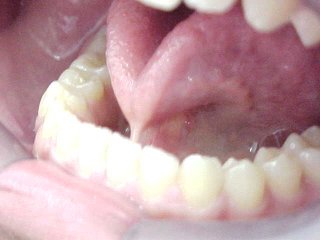

Tratamento cirúrgico da "Língua Presa". Frenectomia ou Frenulotomia Lingual

| Esta técnica cirúrgica destina-se à liberação dos movimentos funcionais da língua . Neste caso a inserção mais anterior se mostra aderida à gengiva: